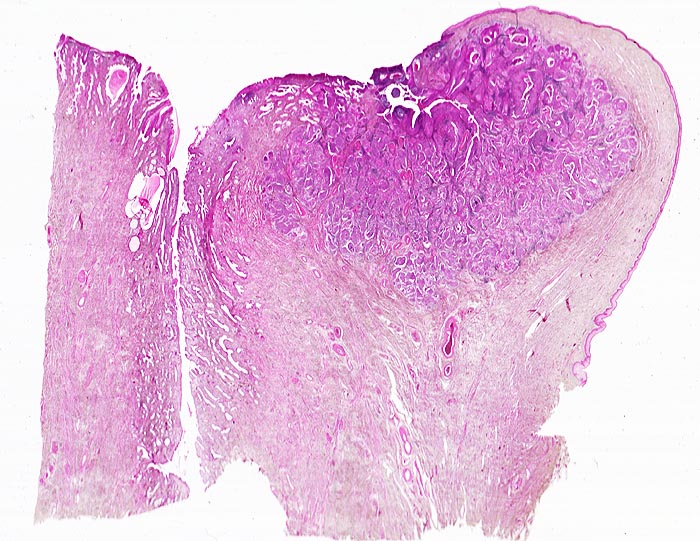

Die Tumorzellen liegen einzeln oder in kleinen Verbänden und ganzen Gewebsfragmenten. Die polymorphen Kerne sind vergrössert und enthalten verklumptes unregelmässig verteiltes Chromatin und grosse Nukleolen. Gut differenzierte Karzinome erkennt man am breiten und oft verhornten Zytoplasma. Längliche bis fadenförmige Tumorzellen mit pyknotischen Kernen können als einziger Hinweis auf das Vorliegen eines Karzinoms vorhanden sein. Wenig differenzierte Karzinome haben polymorphe und schlechter erhaltene Kerne. Der Hintergrund ist meist detritisch und oft hämorrhagisch. Ulzeration, Einblutungen und bakterielle Infektionen beeinflussen den Erhaltungszustand und die Art der abgestrichenen Zellen. Ist die Oberfläche eines ulzerierten Karzinoms von einem Fibrinschorf bedeckt, enthalten die Ausstriche lediglich Detritus, Granulozyten und Erythrozyten, aber keine Tumorzellen. Die Sensitivität für die Karzinomdiagnose ist aus diesem Grund geringer als für die Diagnose eines Carcinoma in situ.

Unten werden drei Fallbeispiele mit histologischer Korrelation gezeigt.